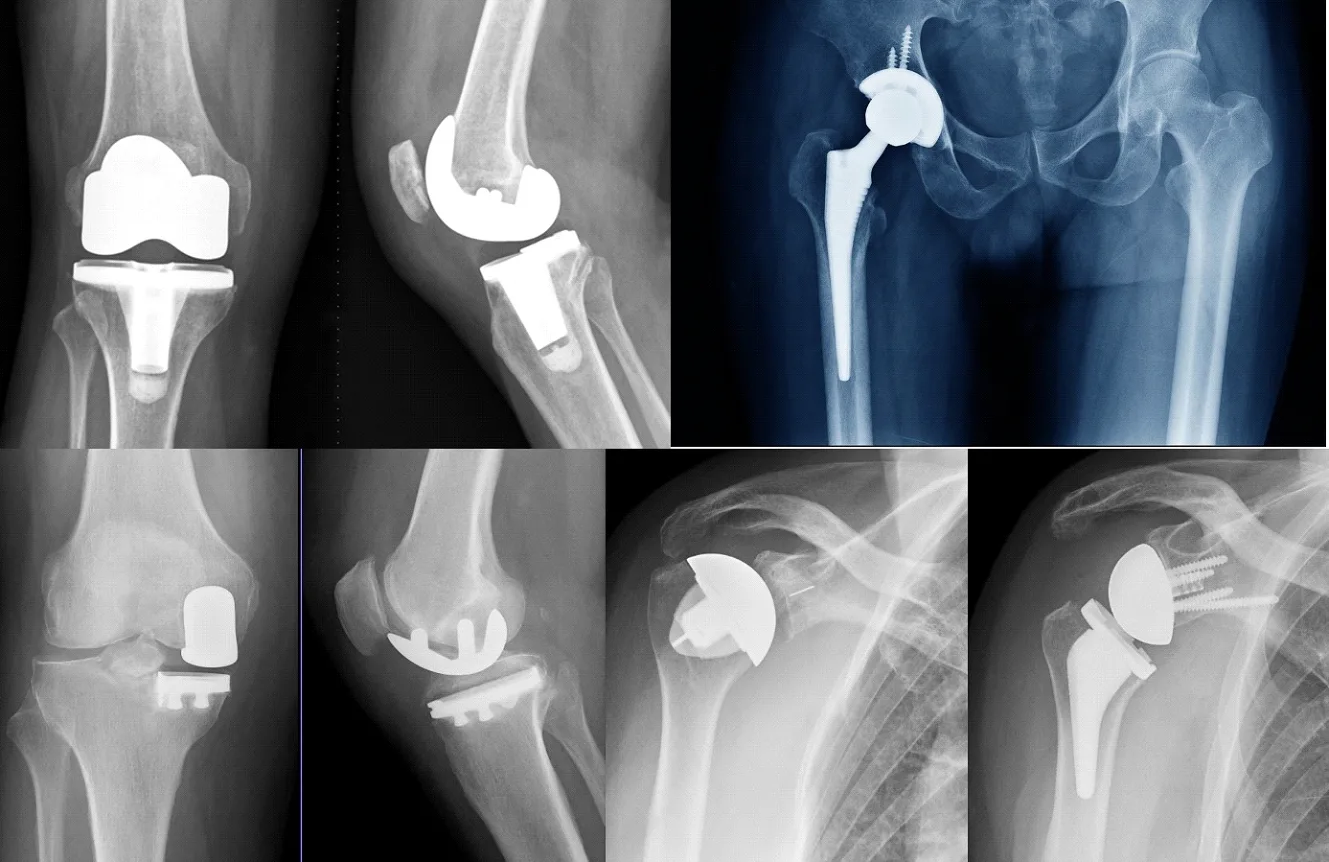

Diz protezi, kıkırdağı ileri derecede yıpranmış diz ekleminde ağrıyı azaltmak ve günlük fonksiyonu kalıcı biçimde iyileştirmek için, hasarlı eklem yüzeylerinin çıkarılıp onların yerine biyouyumlu yapay yüzeylerin yerleştirilmesi esasına dayanır. Ameliyatın başarısı yalnız ameliyat anındaki işçilikten değil, doğru hasta seçimi, titiz planlama, uygun implant seçimi ve dengeli yumuşak doku restorasyonundan etkilenir. Genel hedef, ağrısız ve stabil bir diz ile fizyolojik hizalanma ve güvenli hareket açıklığı elde etmektir.

İlk aşamada eklemdeki osteofitlerin ve yıpranmış kıkırdak artıklarının temizlenmesi yapılır. Ardından kemik kesileri planlanan eksenlere uygun biçimde gerçekleştirilir. Tibia tarafında kesim genellikle mekanik eksene dik ve arzu edilen posterior eğim açısına göre yapılır; bu kesim implantın altında düzgün ve geniş bir temas yüzeyi sağlar. Femur tarafında distal ve ön arka kesiler, femoral komponentin boyutuna ve kılavuzların belirlediği açı ve dönüklüğe uygun yapılır. Bu aşamada iki ana felsefe kullanılır: ölçüye dayalı rezeksiyon ve aralık dengesi. Ölçüye dayalı rezeksiyon, kemiği implant kalınlığına uygun miktarda çıkarıp doğal anatomiye yaklaşmayı hedeflerken; aralık dengesi tekniği, tam ekstansiyon ve 90 derece fleksiyonda iç ve dış kollateral yapıların gerilimini eşitleyerek simetrik boşluklar elde etmeyi amaçlar. Pratikte çoğu cerrah bu iki yaklaşımı birlikte ve hastaya özel şekilde harmanlar.

Kemik kesileri tamamlandıktan sonra deneme (trial) komponentleri yerleştirilir ve diz tüm hareket açıklığı boyunca test edilir. Tam açma ve 90 derece bükmede aralıkların eşitliği, patellanın ortalanması, stabilite, impingement olmaması ve alt ekstremitenin genel ekseni değerlendirilir. Uygun boylar ve açıların doğrulandığı noktada kalıcı komponentlerin tespiti yapılır. Tespit yöntemi kemik kalitesi, yaş ve implant tasarımına göre çimentolu, çimentosuz veya hibrit olabilir. Çimentolu uygulamalarda polimetilmetakrilat dikkatle hazırlanır, kemik yüzeylerine basınçlı uygulanır ve komponentler istenen pozisyonda sabitlenir. Çimentosuz tasarımlarda ise kemiğe sıkı oturan, poröz yüzeyli implantlar zamanla kemikle bütünleşecek şekilde yerleştirilir.